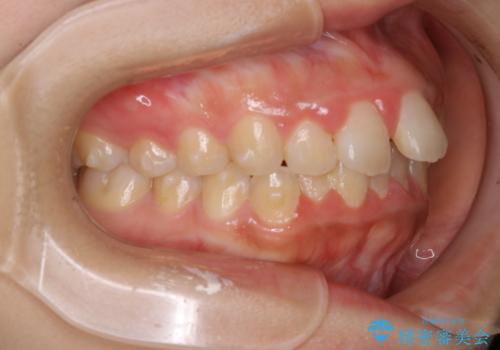

- 4年ほど前から地元の歯科医院にてインビザライン治療を行っていたが、引っ越し後に通いづらくなってしまったため、治療が途中で止まってしまっているとの事で来院されました。性格的にインビザラインの継続した使用が難しいとのことで、ワイヤー装置にて最終仕上げを行いました。

インビザラインは20時間以上の装着を厳守して頂くことで治療効果が期待できる治療となります。固定式のワイヤー装置に切り替えることで短期間で歯並びを整えることができ、大変喜んでいただけました。